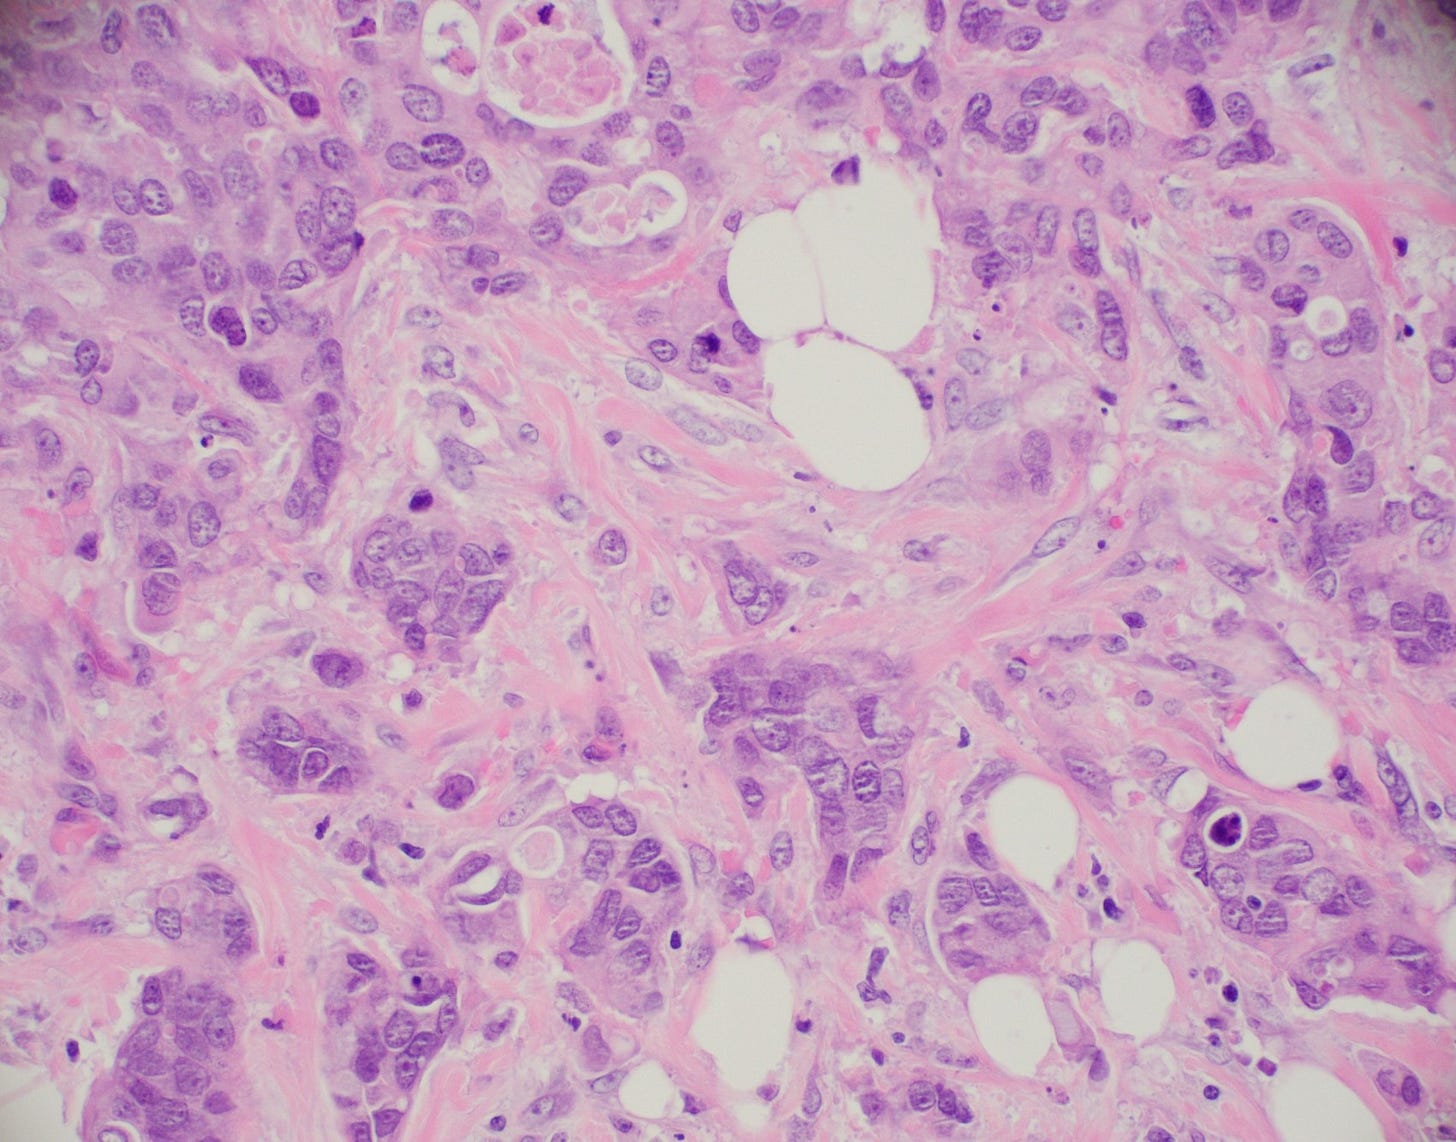

Classic lobular carcinoma - microscopic images

The premalignant precursors of classic lobular carcinoma are classic lobular carcinoma in situ (classic LCIS), its variants florid LCIS and pleomorphic LCIS, and atypical lobular hyperplasia (ALH).

Lobular carcinoma

Lobular carcinoma is a common type of invasive breast carcinoma (10% of cases). It is characterized by the loss of cellular adhesion with dyscohesive tumor cells arranged in single file or as individual single cells. The cells show a loss of 16q (the CDH1 gene located at 16q22.1 encodes E-cadherin, essential in forming the adherens junction responsible for cell adhesion). Loss of E-cadherin protein expression by immunohistochemistry is helpful but not required for diagnosis.

Lobular carcinoma of the breast typically presents with vague findings such as thickening, swelling or a poorly defined breast mass. In general, it is more difficult to detect with mammography (due to infrequent calcifications) and more often presents as a larger tumor with nodal involvement compared to invasive ductal carcinoma of no special type. It is more frequently bilateral and multifocal.

A mastectomy may be preferred because of the risk of local recurrence. These patients generally respond better to hormonal therapy compared to those with invasive ductal carcinoma of no special type. However, their response to radiation therapy is comparable, while their response to chemotherapy is less favorable